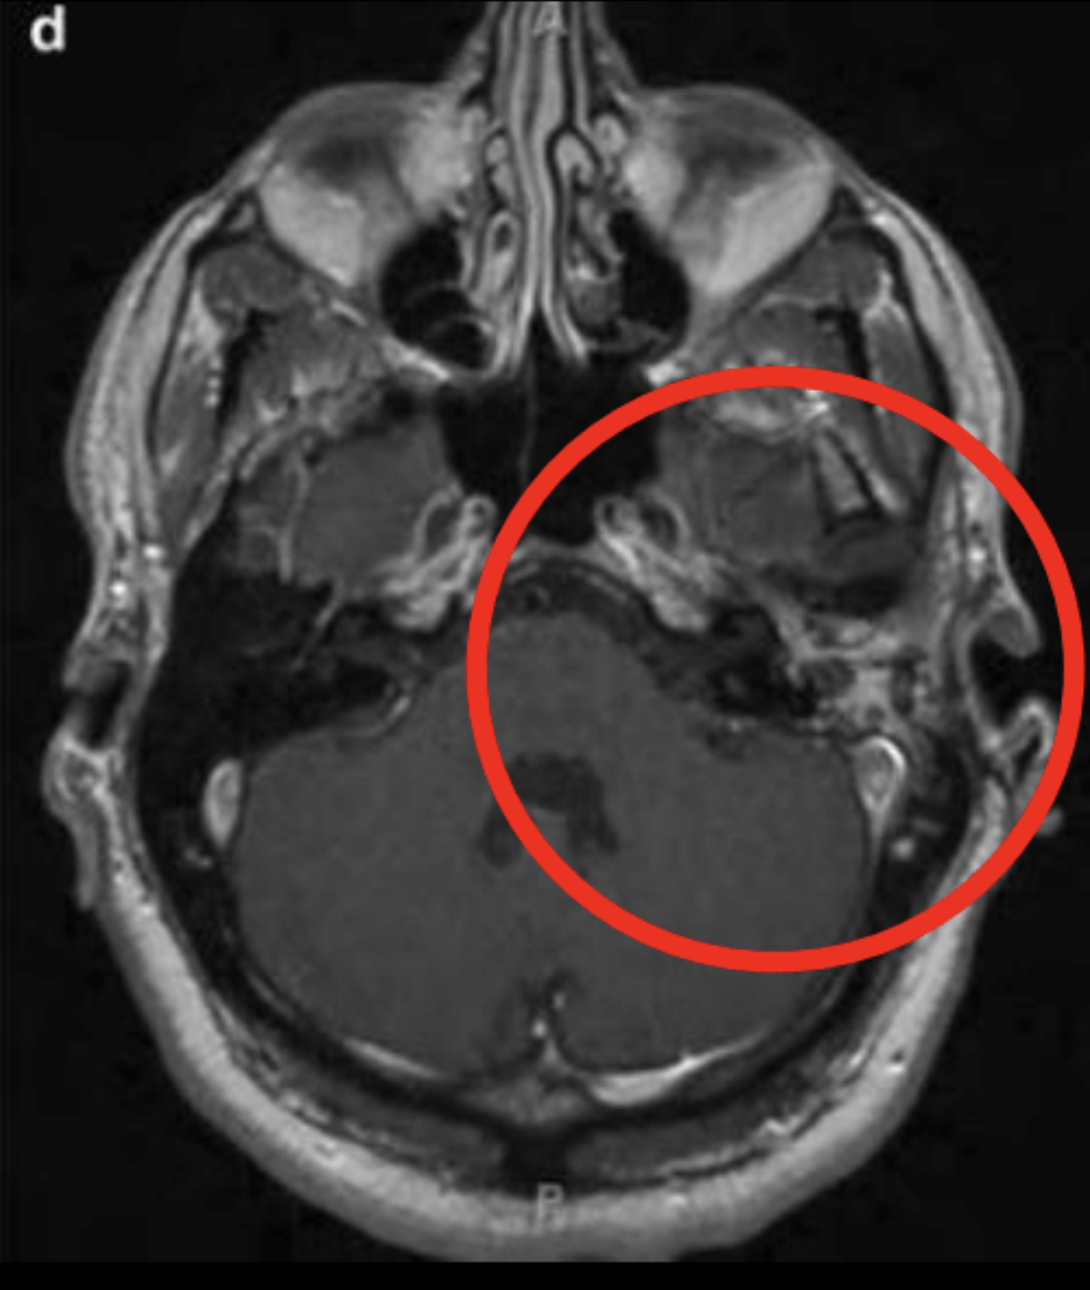

¿Para qué nos sirve la RM en otomastoiditis? ¿Qué ves en la imagen?

Para ver extensión intracraneal

Veo meningitis por la infección